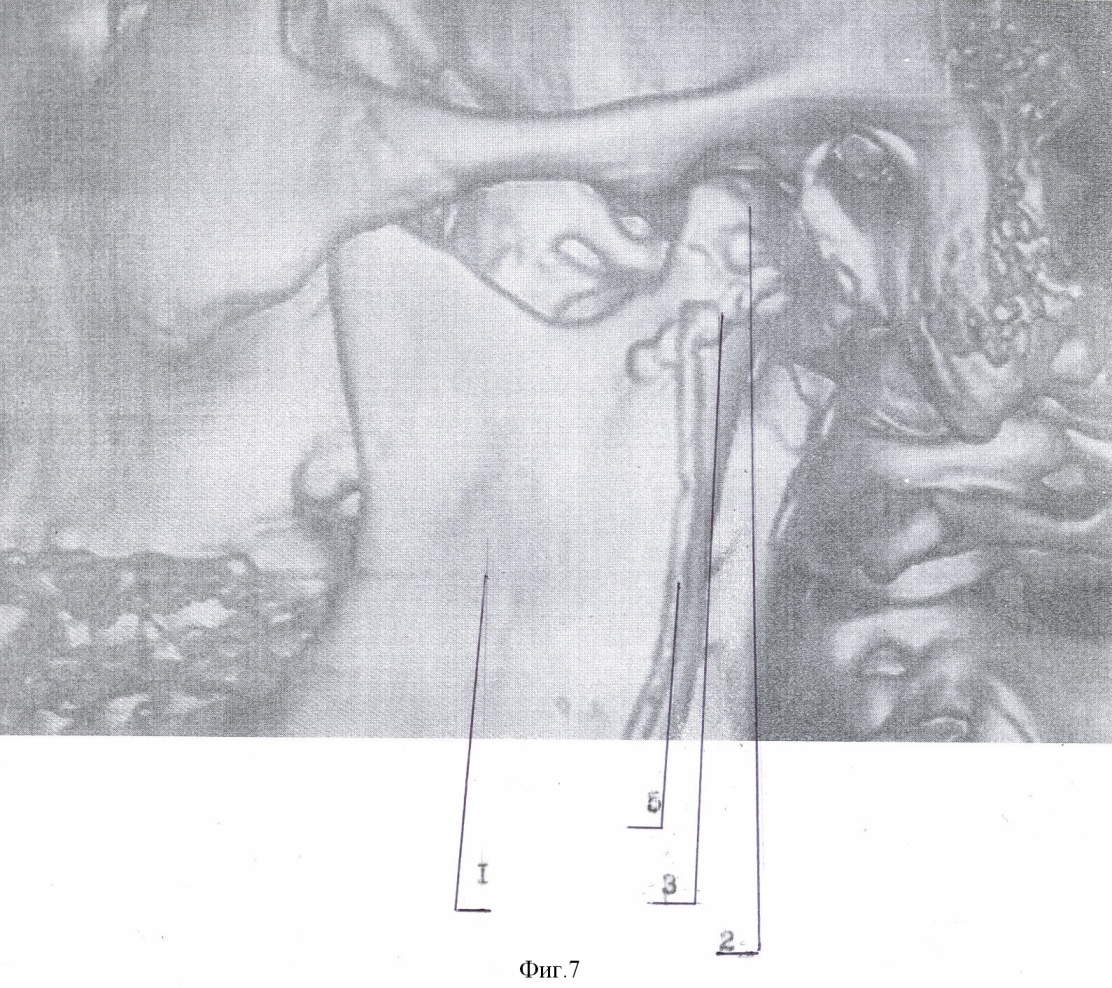

Способ осуществляют следующим образом. Типичным доступом через разрез кожи в подчелюстной области, окаймляющим угол нижней челюсти, осуществляют послойный доступ к линии перелома поднадкостнечно по латеральной поверхности ветви. Вывихнутый диссектором малый фрагмент вместе с суставной капсулой выводят в вырезку. Суставную капсулу рассекают вперед на 0,3-0,5 см. Отломок суставного отростка освобождают от суставной капсулы и выводят из раны. Фиброзные наложения раневых поверхностей костей удаляют. После оценки состояния отломка к участку, свободному от суставной поверхности, по заднему краю фиксируют микропластину (Т, Н, Х, L, Y-образной формы). Свободный конец микропастины изгибают для плотного прилегания к большему фрагменту по задней и латеральной поверхности ветви. Из суставной капсулы формируют ложе в суставной впадине. Малый фрагмент с подготовленной микропластиной устанавливают в ложе в анатомическом положении. Суставную капсулу над суставным бугорком укрепляют узловыми швами ПДС 4/0. Большой фрагмент репонируют на установленную в ложе конструкцию. Свободный конец микропластины фиксируют к заднелатеральной поверхности большего фрагмента микрошурупами. Осуществление способа и результат продемонстрированы на чертежах 1-8: фиг.1 – компьютерная томограмма (реконструкция) нижней челюсти, левая боковая; фиг.2 – компьютерная томограмма (реконструкция) нижней челюсти, вид сзади; фиг.3 – компьютерная томограмма (реконструкция) нижней челюсти, вид косо сзади; фиг.4 – собранная конструкция, вид сзади; фиг.5 – собранная конструкция, вид спереди; фиг.6 – компьютерная томограмма (реконструкция), вид спереди, после операции; фиг.7 – компьютерная томограмма (реконструкция) нижней челюсти, левая боковая, после операции; фиг.8 – компьютерная томограмма (реконструкция) нижней челюсти, левый суставной отросток, вид изнутри, после операции: где 1 – нижняя челюсть, 2 – отломок суставного отростка, 3 – титановая микропластина, 4 – микрошуруп, 5 – дренажная трубка.

Пример. Больной П., 14 лет поступил в отделение челюстно-лицевой хирургии ДККБ 20.04.07 г. с диагнозом: травматический тройной перелом нижней челюсти; перелом – вывих головки суставного отростка слева, перелом суставной головки справа без смещения, косой центральный перелом тела нижней челюсти со смещением (фиг. 1, 2, 3). 23.04.07 г. под общим обезболиванием выполнено оперативное вмешательство – открытая репозиция, металлоостеосинтез суставной головки слева Т-образной микропластиной, открытая репозиция, металлоостеосинтез косого перелома тела нижней челюсти двумя параллельными минипластинами. Типичным доступом через разрез кожи в подчелюстной области слева, окаймляющим угол нижней челюсти 1, осуществлен послойный доступ к линии перелома поднадкостнечно по латеральной поверхности ветви нижней челюсти. При помощи диссектора малый фрагмент мобилизован и вывихнут в вырезку вместе с суставной капсулой. Суставная капсула рассечена вперед на 0,5 см. Отломок суставного отростка 2 освобожден от суставной капсулы и выведен наружу. Фиброзные наложения на раневых поверхностях фрагментов удалены. По заднему краю отломка, по поверхности, свободной от суставной, при помощи микрошурупов 4 фиксирована Т-образная титановая микропластина 3, изогнутая для плотного прилегания к заднелатеральной поверхности большего фрагмента (фиг. 4, 5). Суставная капсула перемещена и расправлена в суставной ямке. В образованное ложе уложена конструкция в анатомическом положении. На края суставной капсулы над суставным бугорком наложены 2 узловых шва ПДС 4/0, обеспечивающие плотный охват отломка. Больший фрагмент репонирован на установленную конструкцию. Свободный конец микропластины 4 после небольшой коррекции изгиба фиксирован к заднелатеральной поверхности большего фрагмента микрошурупами 3. Рана послойно ушита с оставлением активного дренажа 5. Подчелюстным разрезом осуществлен послойный доступ к линии перелома тела нижней челюсти. Произведена типичная репозиция костных отломков, остеосинтез двумя параллельными минипластинами. Рана послойно ушита.

В послеоперационном периоде проводилась иммобилизация челюсти при помощи шин Васильева с межчелюстными вытяжениями. На контрольно компьютерной томограмме (26.04.07 г., фиг. 6, 7, 8) выявлено удовлетворительное стояние костных отломков. Больной выписан 4.05.07 г на дальнейшее амбулаторное лечение.